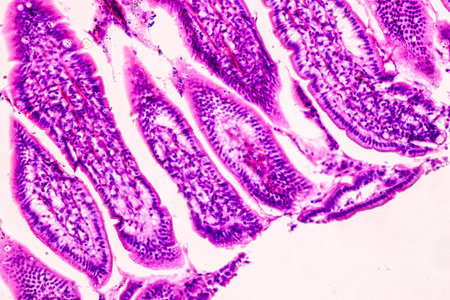

Small intestine with villi under the microscope 100x